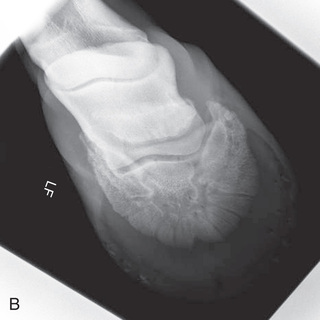

Digit/foot: P-III (distal phalanx, coffin bone) P-II (middle phalanx) P-I (proximal phalanx-pastern) Proximal interphalangeal joint (pastern joint) joint | DP (Standard) (Fig. 24.62B,C) | Dorsal 45-degree proximal–palmarodistal (D45Pr-PaDi) | Foot slightly forward on image receptor. | Perpendicular to foot axis at MSP (midsagittal plane) at area of interest with beam angled ~45 degrees to ground |

| Lateral (Standard) (Fig. 24.62D) | Lateromedial | On a block to elevate limb for P-III; resting on ground for other views. | 90 degrees lateral to MSP, parallel to ground on area of interest: coronary band for PIII | |

| Lateral-interdigit (Optional) | Lateromedial (mediolateral) with interdigital film | Receptor between digits. Easiest with patient in lateral recumbency but can be completed standing with foot raised. | 90 degrees laterally from MSP to radiograph the lateral claw. 90 degrees medially from MSP medially to radiograph the medial claw. | |